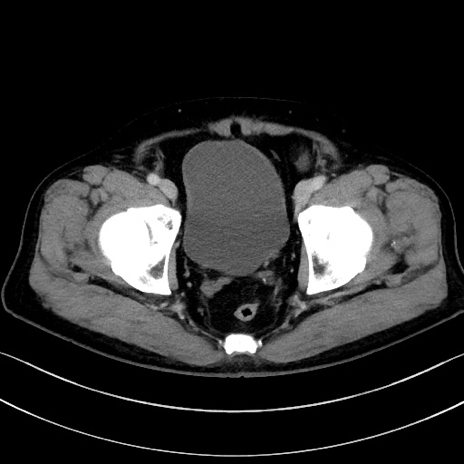

症例15(横断像)

【症例】70歳代男性

【主訴】腹痛

【現病歴】今朝から腹痛あり。全体的に痛い。特に左上の方。排ガスが今日はない。冷や汗が出る。

【既往歴】直腸癌術後

【身体所見】左側腹部〜上腹部に圧痛あり。腹膜刺激症状明らかなではない。軽度反跳痛。左下腹部に術後瘢痕あり。

【データ】WBC 7700、CRP 0.02